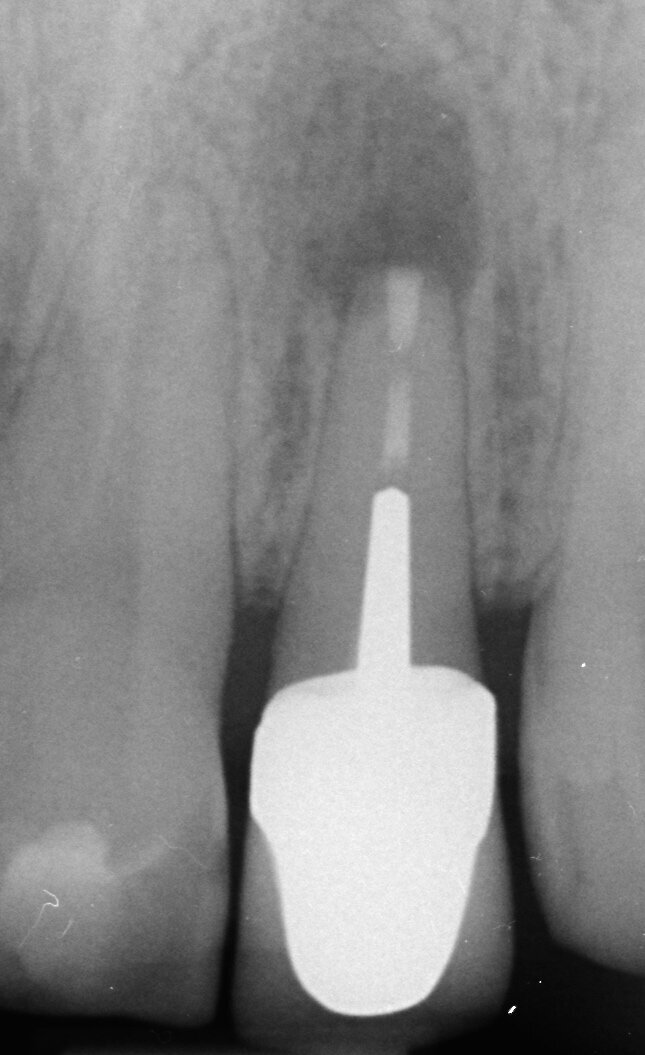

Per evitare l’estrusione di materiale da otturazione del canale radicolare in denti immaturi con apici aperti, si utilizza MTA come sigillo apicale. I risultati di molti studi hanno dimostrato che l’MTA induce più spesso la formazione di tessuto duro apicale e che il suo uso è associato ad una minore infiammazione rispetto ad altri materiali di prova (Simon et al. 2007) (Figg. 2a-2g).

Apecificazione